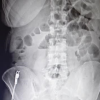

İSTANBUL - Kadınlarda en sık görülen kanser türü olan rahim ağzı kanseri her yıl binlerce kadını etkilerken, tedavide erken tanı ise hayat kurtarıyor. Konuya ilişkin uyarılarda bulunan Prof. Dr. Ahmet Kale, "Kadınlardan, pandemi nedeniyle bu hastalık ile alakalı kontrollerini ve tedavilerini aksatmamasını önemle rica ediyoruz" diye konuştu. Prof. Dr. Ahmet Kale, rahim ağzı kanseri farkındalık ayı dolayısıyla serviks (rahim ağzı) kanseri hakkında uyarılarda bulundu. Kale, "Ocak ayı (serviks) kanseri ya da daha Türkçe ifadeyle rahim kanseri ayı. Bu dönemde bayanlardan özellikle bu konudaki tedavilerini ve bu hastalıkla ilgili takiplerini aksatmamalarını istiyoruz" sözlerini kullandı. "Kanamalı durumlarda bir an önce hastaneye başvurulmalı" Pandemi süreci nedeniyle hastaneye gelmekten çekinen vatandaşlar olduğunu belirten Prof. Dr. Kale, "Bu aslında doğru bir uygulama değil. Çünkü Kartal Doktor Lütfi Kırdar Eğitim ve Araştırma Hastanesi'nde ve Şehir Hastanesi'nde tüm pandemi tedbirlerinin alınmasıyla birlikte pandeminin başından beri tüm ameliyatlar güvenli bir şekilde tüm tedbirler alarak yapılıyor" dedi. Kanser hastalarının ameliyat süreçlerini uzatmaları sonucu durumun daha tehlikeli noktalara ulaşabileceğini aktaran Prof. Dr. Kale," Mesela rahim kanseri olan ya da rahim ağzı kanseri olan bir hasta Covid nedeniyle hastaneye gelmezse o süreçte hastalık daha ileri bir boyuta taşınacak belki de cerrahi müdahale süresini dahi aşmış olacak. Onun için hastalarımız, herhangi bir şüphede, vajinal kanama veya anormal kanamalı durumlarda bir an önce hastaneye başvurup erken tanı ve tedavi olursa bu hastalarımız belki çok uzun süre yaşamış olacak. "Sağlığınızı lütfen ertelemeyin" Erken tanının hayat kurtaracağını vurgulayan Prof. Dr. Kale, "Kanser olmayan hastalarımızdan, kanaması olan kişiler eğer erken dönemde başvurursa, bu hastalarımıza daha sınırdayken henüz yakalanmadan önce erken dönemde müdahale edip onları bir an önce sağlığına kavuştururuz. Son olarak şunu söylemek istiyorum. Sağlığınızı lütfen ertelemeyin. En ufak hastalık belirtisinde bir sağlık kuruluşuna başvurun. Başhekimimiz Profesör Doktor Recep Demirhan'ın başkanlığında ve başhekimliğinde biz sağlık ordusu olarak 7/24 tüm halkımıza hizmet etmekten dolayı onur duyarız. Tüm halkımızı en ufak bir sıkıntıda Kartal Doktor Lütfi Kırdar Şehir Hastanesi'ne bekliyoruz" sözlerini kullandı. "Hocalarımız her konuda çok dikkatli davrandılar"" Rahim ağzı ameliyatı sonrası konuşan hastalardan Emine Abdioğlu, "Ameliyat çok güzel geçti. Gayet de başarılıydı. Kimse korkmasın, hocalarımız çok ilgiliydiler. Herkesin gelmesini tavsiye ederim" diye konuşurken tedavisi tamamlanan bir diğer hasta olan Gökçen Kalender ise, "Ameliyatım iyi geçti. Şu an daha iyiyim. Pandemi nedeniyle açıkçası ameliyat konusunda çekiniyorduk. Hocalarımız her konuda çok dikkatli davrandılar. Memnun kaldık" diye konuştu.